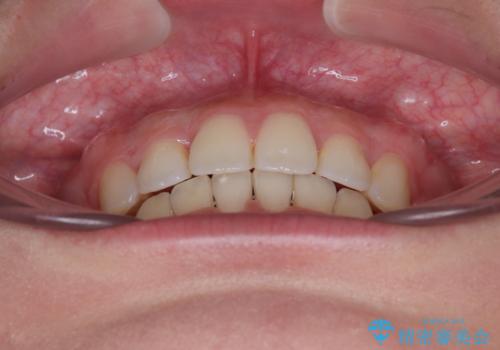

- 全体的なデコボコと口元の突出感を改善したいとのことで来院された患者様です。

このままデコボコを整えるとさらに突出感が増すため、上下左右の第一小臼歯を抜歯し、ワイヤー装置にて矯正しました。

結婚式で途中装置を外した時期がありましたが、2年で治療を終えることができました。